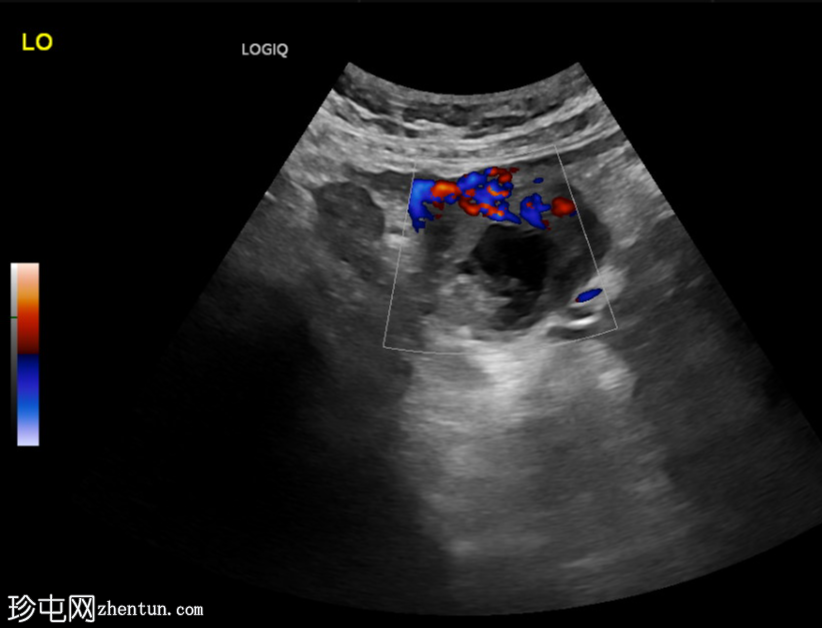

超声检查

横切面

左侧卵巢明显增大,可见一囊肿,大小约3.2 x 2.3 cm,呈火环征,可能为黄体囊肿。左侧卵巢与子宫之间可见一管状结构,直径约1.3 cm,内含浑浊液体,未见血管,最可能为输卵管积血。以上特征提示可能为左侧异位妊娠。

未见宫内妊娠囊。